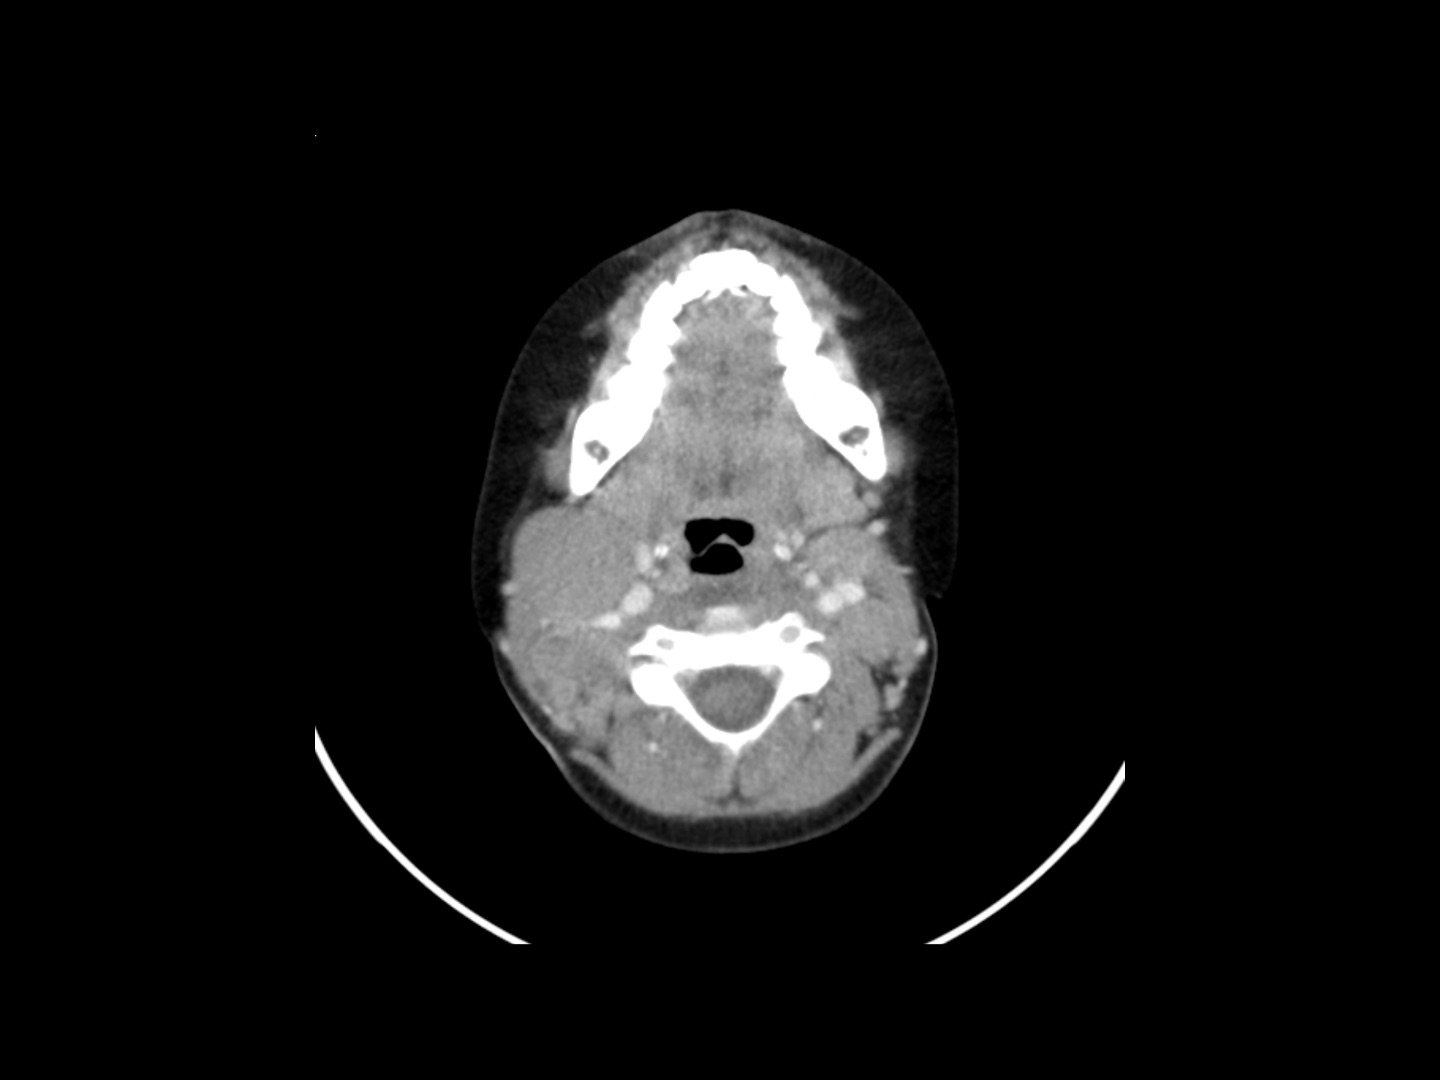

Multiples Myelom (typisch: Schrotschussschädel)

Multipler Müll-Gnom (von Schrot getroffene Schädeltonne)

Das multiple Myelom ist ein Plasmazelltumor, der vom Knochenmark ausgeht. Typisch sind multiple Osteolysen (Schrotschussschädel).